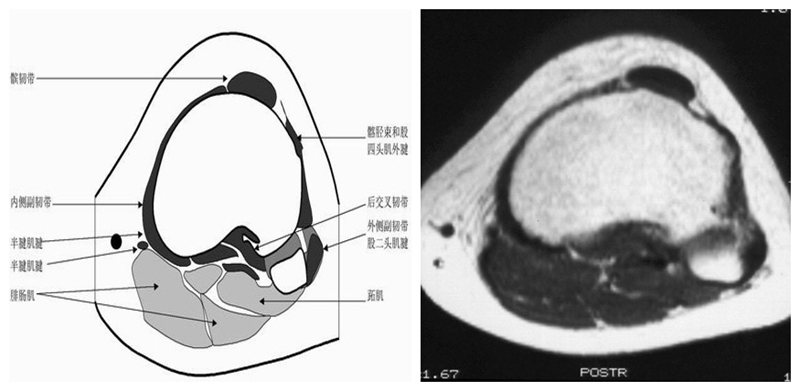

膝关节横断面MRI解剖

三维影像首选的方位,便于与CT比较,可准确地展现髌骨内外侧关节面。